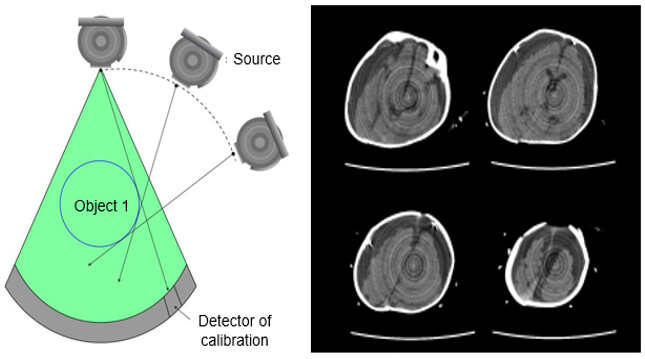

Ring Artifacts

If one of the detectors is out of calibration on a scanner, the detector will give a consistently erroneous reading at each angular position, resulting in a circular artifact.

A scanner with solid-state detectors, where all the detectors are separate entities, is in principle more susceptible to ring artifacts than a scanner with gas detectors, in which the detector array consists of a single xenon-filled chamber subdivided by electrodes.

The presence of circular artifacts in an image is an indication that the detector gain needs recalibration or may need repair services.